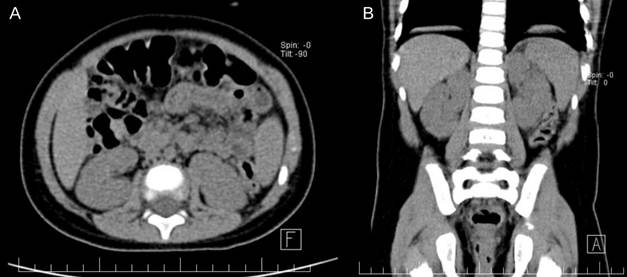

Posterior al procedimiento se tomó una radiografía del abdomen durante la hospitalización, sin identificar cálculos residuales. El paciente fue dado de alta al día siguiente y fue reevaluado en 10 días con una tomografía axial computarizada abdominal y pélvica. El catéter uretral se retiró 10 días después del procedimiento y la tomografía no mostró cálculos en los riñones, los uréteres ni en la vejiga. La piedra resultó de oxalato de calcio. En el seguimiento, el niño no tuvo dificultad para orinar y se encontraba asintomático.